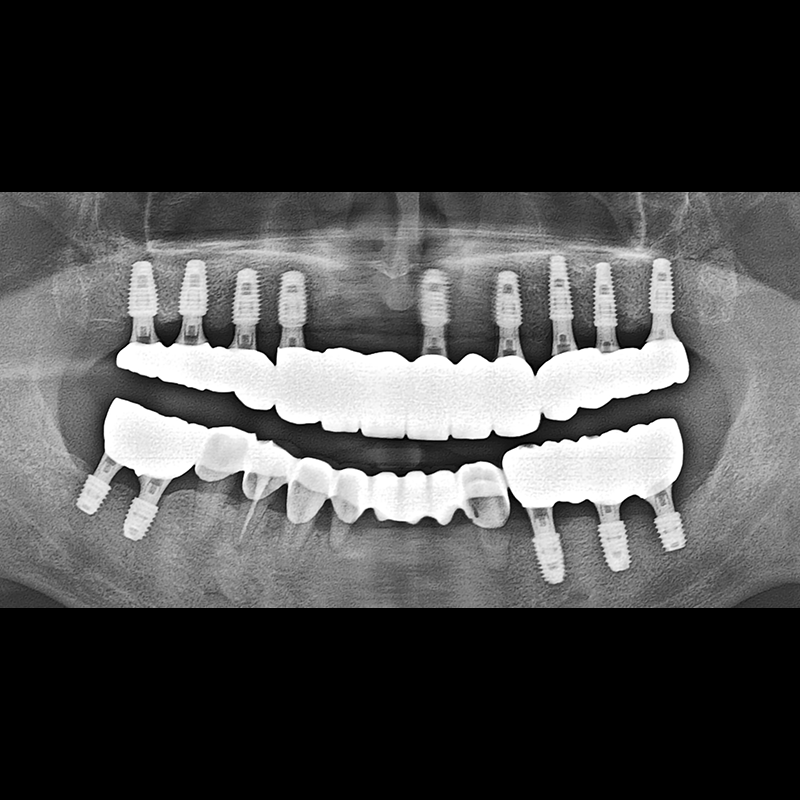

BEFORE AFTER

임플란트 전후사진 2025.05.30

결손된 치아 부분과 살리기 힘든 치아 위치에 임플란트를 식립하였습니다.